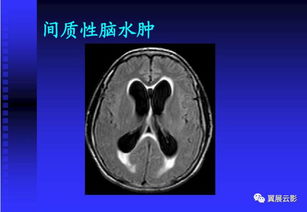

MRI已成為癲癇診斷和處理的主要工具。MRI對哪怕只有很少量水分的增加都可以敏感的發(fā)現(xiàn),且具有骨偽影少的特 點,能更精確地顯示某些癲癇病人CT掃描不能發(fā)現(xiàn)的腦結構改變,如無癥狀的神 經(jīng)膠質(zhì)瘤、胚胎發(fā)育不良神經(jīng)上皮瘤、海綿狀血管瘤、腦梗死、腦出血后及外傷 后腦損傷灶、局灶性腦萎縮和腦穿通畸形等。

對于有微小病灶或頑固性部分性發(fā) 作的病人,如考慮進行手術治療,則進行MRI檢查更為合適。海馬病變引起的顳葉癲癇在癲癇的診斷與治療中占有重要地位。

MRI在診斷 海馬硬化上有特殊的優(yōu)勢。如果癲癇病人經(jīng)CT等檢查已發(fā)現(xiàn)某個病灶,也必須同 時檢查海馬,因為已經(jīng)發(fā)現(xiàn)的病灶也許與病人的癲癎無關,而引起癲癎發(fā)作的真 正原因是海馬硬化。